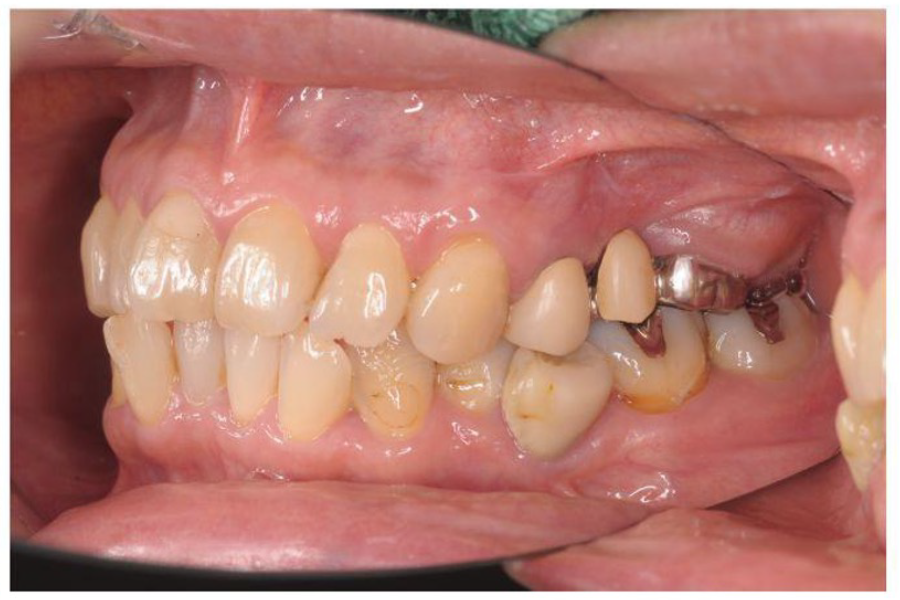

治療前